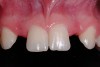

Conversion of the surgical guide to the esthetic provisional was then completed by retrofitting the surgical guide with restorative composite, and then placing the guide back over the provisional copings that were seated on the abutment portion of the one-piece implants, and curing the surgical guide with a curing light (Figure 12). The guide was then reviewed, with the provisionals in the guide, then removal of the provisionals from the vacuform portion of the guide allowed for correction of the marginal portion of the provisionals using a flowable composite material. Shaping the line angles and emergence profile of the provisionals allowed for the proper contours of the provisional to be accomplished (Figure 13). The provisionals were then cemented with a strong temporary cement. The immediate postoperative clinical view can be seen in Figure 14 and Figure 15. The provisionals were immediate, non-functional restorations in centric occlusion and relation, and lateral right and left excursive movements. Figure 16 and Figure 17 show the immediate postoperative radiographic view. Note how the 3-mm diameter implant allows for the adequate space between the root surfaces and the implants placed.

The 3-month postoperative views can be seen in Figure 18 through Figure 20. Note the excellent soft tissue emergence profiles obtained from the properly contoured provisional restorations. After removal of the provisional restorations, further inspection of the contoured emergence profile obtained has been accomplished (Figure 21 and Figure 22). Before impression techniques, transfer copings were seated over the abutment portion of the one-piece implant (Figure 23). A full-arch impression was then taken using medium-body impression material (Take 1 Advanced, Kerr Corporation, Orange, CA) and a regular-body wash material (Take 1 Advanced) to pick up the detail of the emergence profile and impression coping (Figure 24 through Figure 26). After allowing the impression material to set, the impression is then removed from the mouth and inspected (Figure 27). The Take 1 Advanced Medium body has a more rigid set than most other medium materials, so when the coping is placed back in the impression, the possibility of movement during casting is reduced. Please note how the emergence profile obtained has been registered in the impression, and can easily be transferred to the laboratory technician. Laboratory analogues are then placed into the impression coping and forwarded to the laboratory technician for pouring of the casts and final fabrication of the esthetic implant restorations (Figure 28).